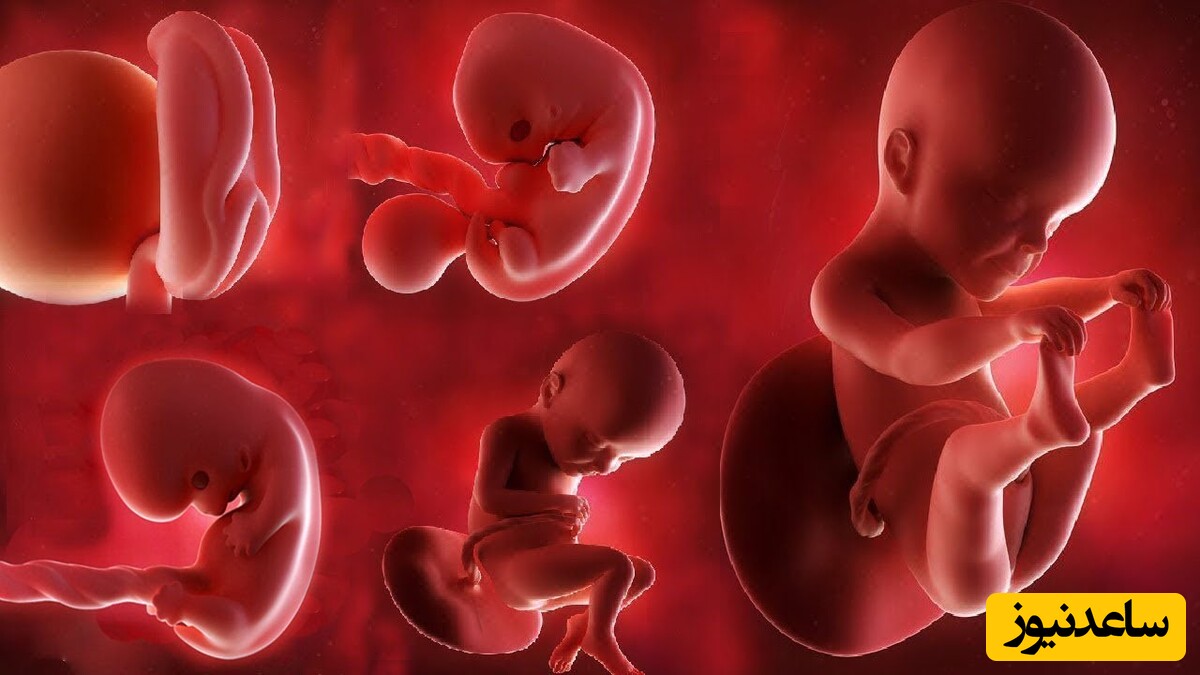

چگونه صدک رشد جنین محاسبه میشود؟

صدک رشد جنین از طریق سونوگرافی و اندازهگیری پارامترهای زیر محاسبه میشود:

دور سر (HC): نشاندهنده رشد مغز و سر جنین.

دور شکم (AC): معیاری برای ارزیابی رشد کبد و وضعیت تغذیهای جنین.

طول استخوان ران (FL): نشاندهنده رشد اسکلتی.

وزن تخمینی جنین (EFW): ترکیبی از اندازهگیریهای بالا برای تخمین وزن کلی.

این دادهها با جداول استاندارد رشد جنین (مانند جداول WHO یا Hadlock) مقایسه میشوند تا صدک رشد مشخص شود. دقت در تعیین سن بارداری (بر اساس اولین روز آخرین قاعدگی یا سونوگرافی اولیه) برای محاسبه دقیق صدک ضروری است.